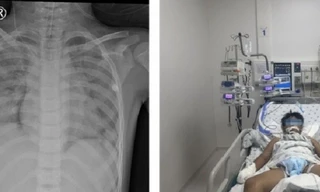

Kết quả của 9 bệnh nhân tham gia vào đoàn hệ đầu tiên sẽ được báo cáo tại ASH. Cho đến nay, tất cả các bệnh nhân đã được điều trị bằng axi-cel và sau điều trị ít nhất 1 tháng.

78% bệnh nhân thấy khối u của họ nhỏ lại hoặc biến mất sau khi điều trị và 67% bệnh nhân cho thấy phản ứng hoàn toàn, trong đó khối u của họ biến mất. Thời hạn của những phản hồi này là 10 tháng. Thời gian sống không bệnh tiến triển trung bình là gần một năm và thời gian sống toàn bộ trung bình là 19 tháng.

Nhóm nghiên cứu đã thu thập máu và CSF từ những bệnh nhân tham gia vào nhóm thuần tập đầu tiên. Các mẫu Dịch não tủy được thu thập thông qua một cổng chuyên dụng, được gọi là bể chứa Ommaya, nằm ngay dưới da đầu và cho phép tiếp cận Dịch não tủy thường xuyên hơn và ít đau hơn so với cách chọc dò tủy sống truyền thống.